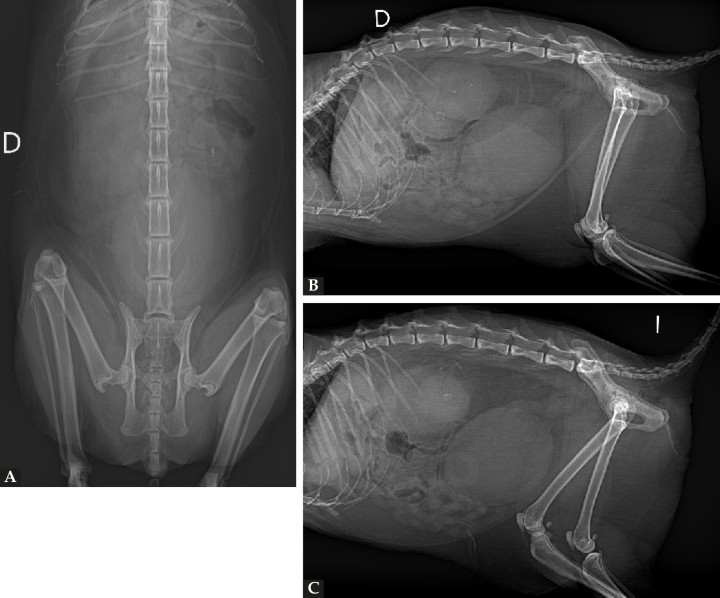

Tras la estabilización del animal, se realizaron radiografías de tórax (compatibles con la normalidad) y de abdomen (Fig. 1).

Radiografías de abdomen. (A) Radiografía ventrodorsal. (B) Radiografía lateral derecha. (C) Radiografía lateral izquierda. D: derecha; I: izquierda.